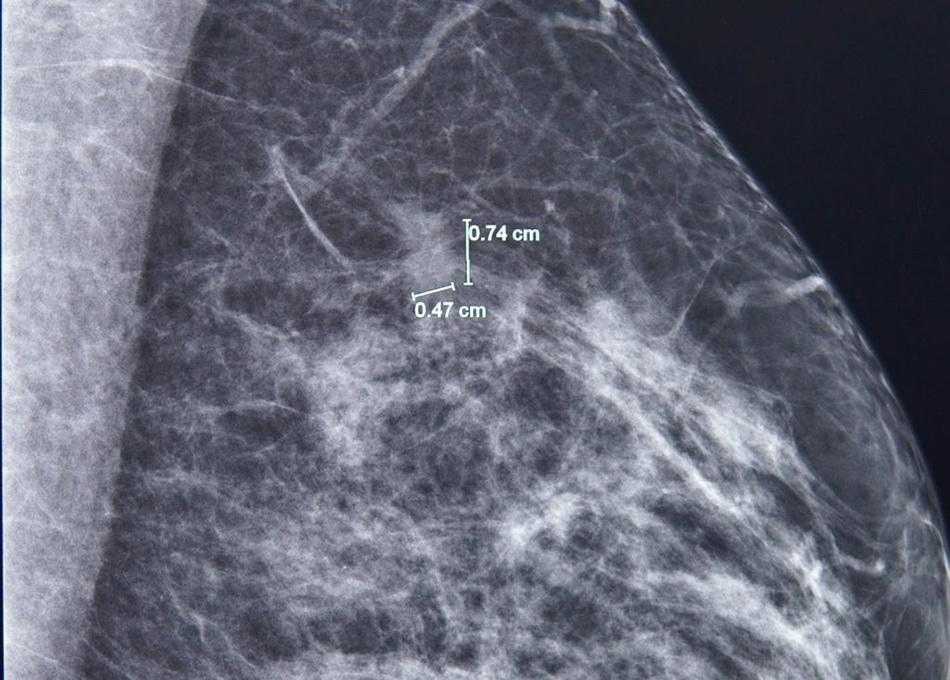

Kết quả nhũ ảnh tìm ra một tổn thương nhỏ, khoảng 7mm ở vú trái. BS.CKI Phùng Ngọc Thư - Trưởng Trung tâm Chăm sóc Tuyến vú FV cho bệnh nhân chụp thêm cộng hưởng từ (MRI) do mô vú bà A. khá đặc, và bác sĩ Thư đã phát hiện thêm một nốt tổn thương khác, chỉ 3mm.

Phát hiện một tổn thương 7mm ở vú trái bằng chụp nhũ ảnh.